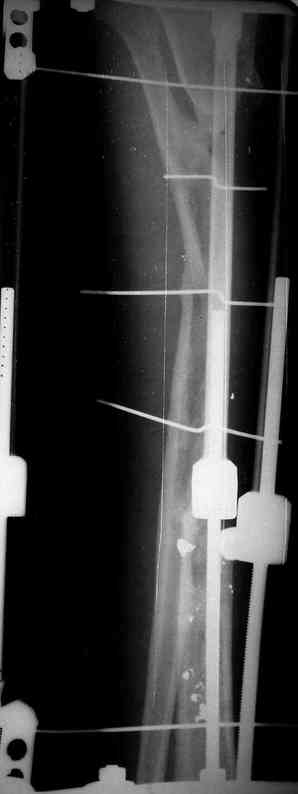

Я думал, что в нижнем отделе голени без мягкотканнего покрытия будет сложно проведения тибиализацию, но твой пример показывает - метод работает даже в таких трудных условиях.

Правда те мои случаи были сделаны давно, еще в Латинской Америке, и конечно качество исполнения отстает от идеалов, но, несмотря на отсутствие нормальных спиц с упором, метод сработал в свое время.

Приходилось встречать замещенные дефекты малоберцовой костью без применения метода Идизарова, и при соблюдении осторожности хрупкая малоберцовая за короткое время под вождействием нагрузки утолщались в диаметре.